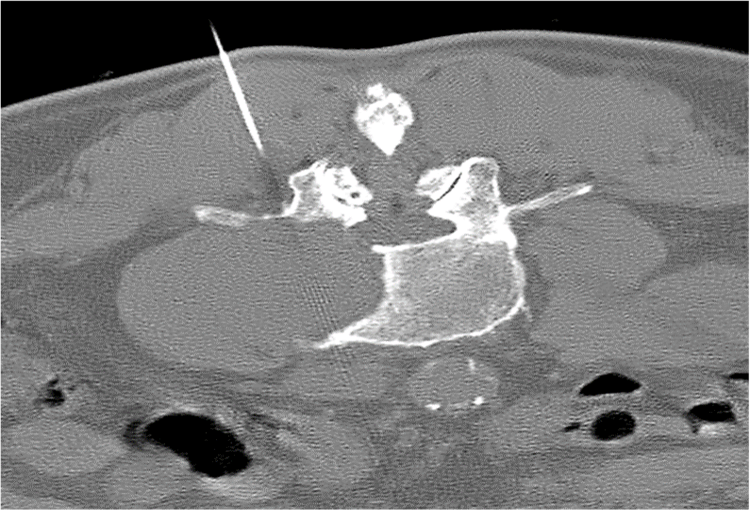

120 kV / 20 mAs / 1 mm

Before FBP (Noise 189) VS After ClariCT.AI (Noise 46) 76% Denoising